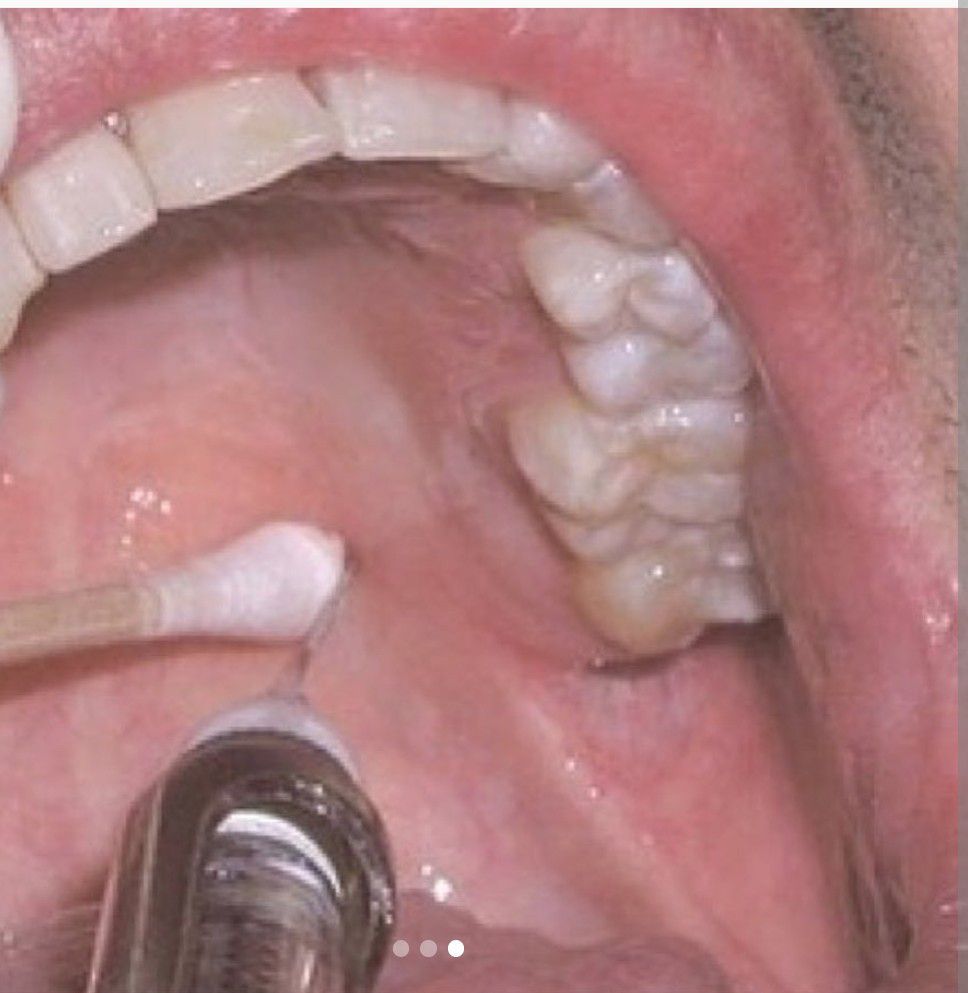

The greater palatine nerve block is useful when treatment is necessary on the palatal aspect of the maxillary premolar and molar dentition. 💉 A 25- or 27-gauge long needle ➕ Better to apply pressure for a minute before the insertion. 📍 The greater palatine nerve block is 1 cm medial to the junction of the maxillary second and third molars. .